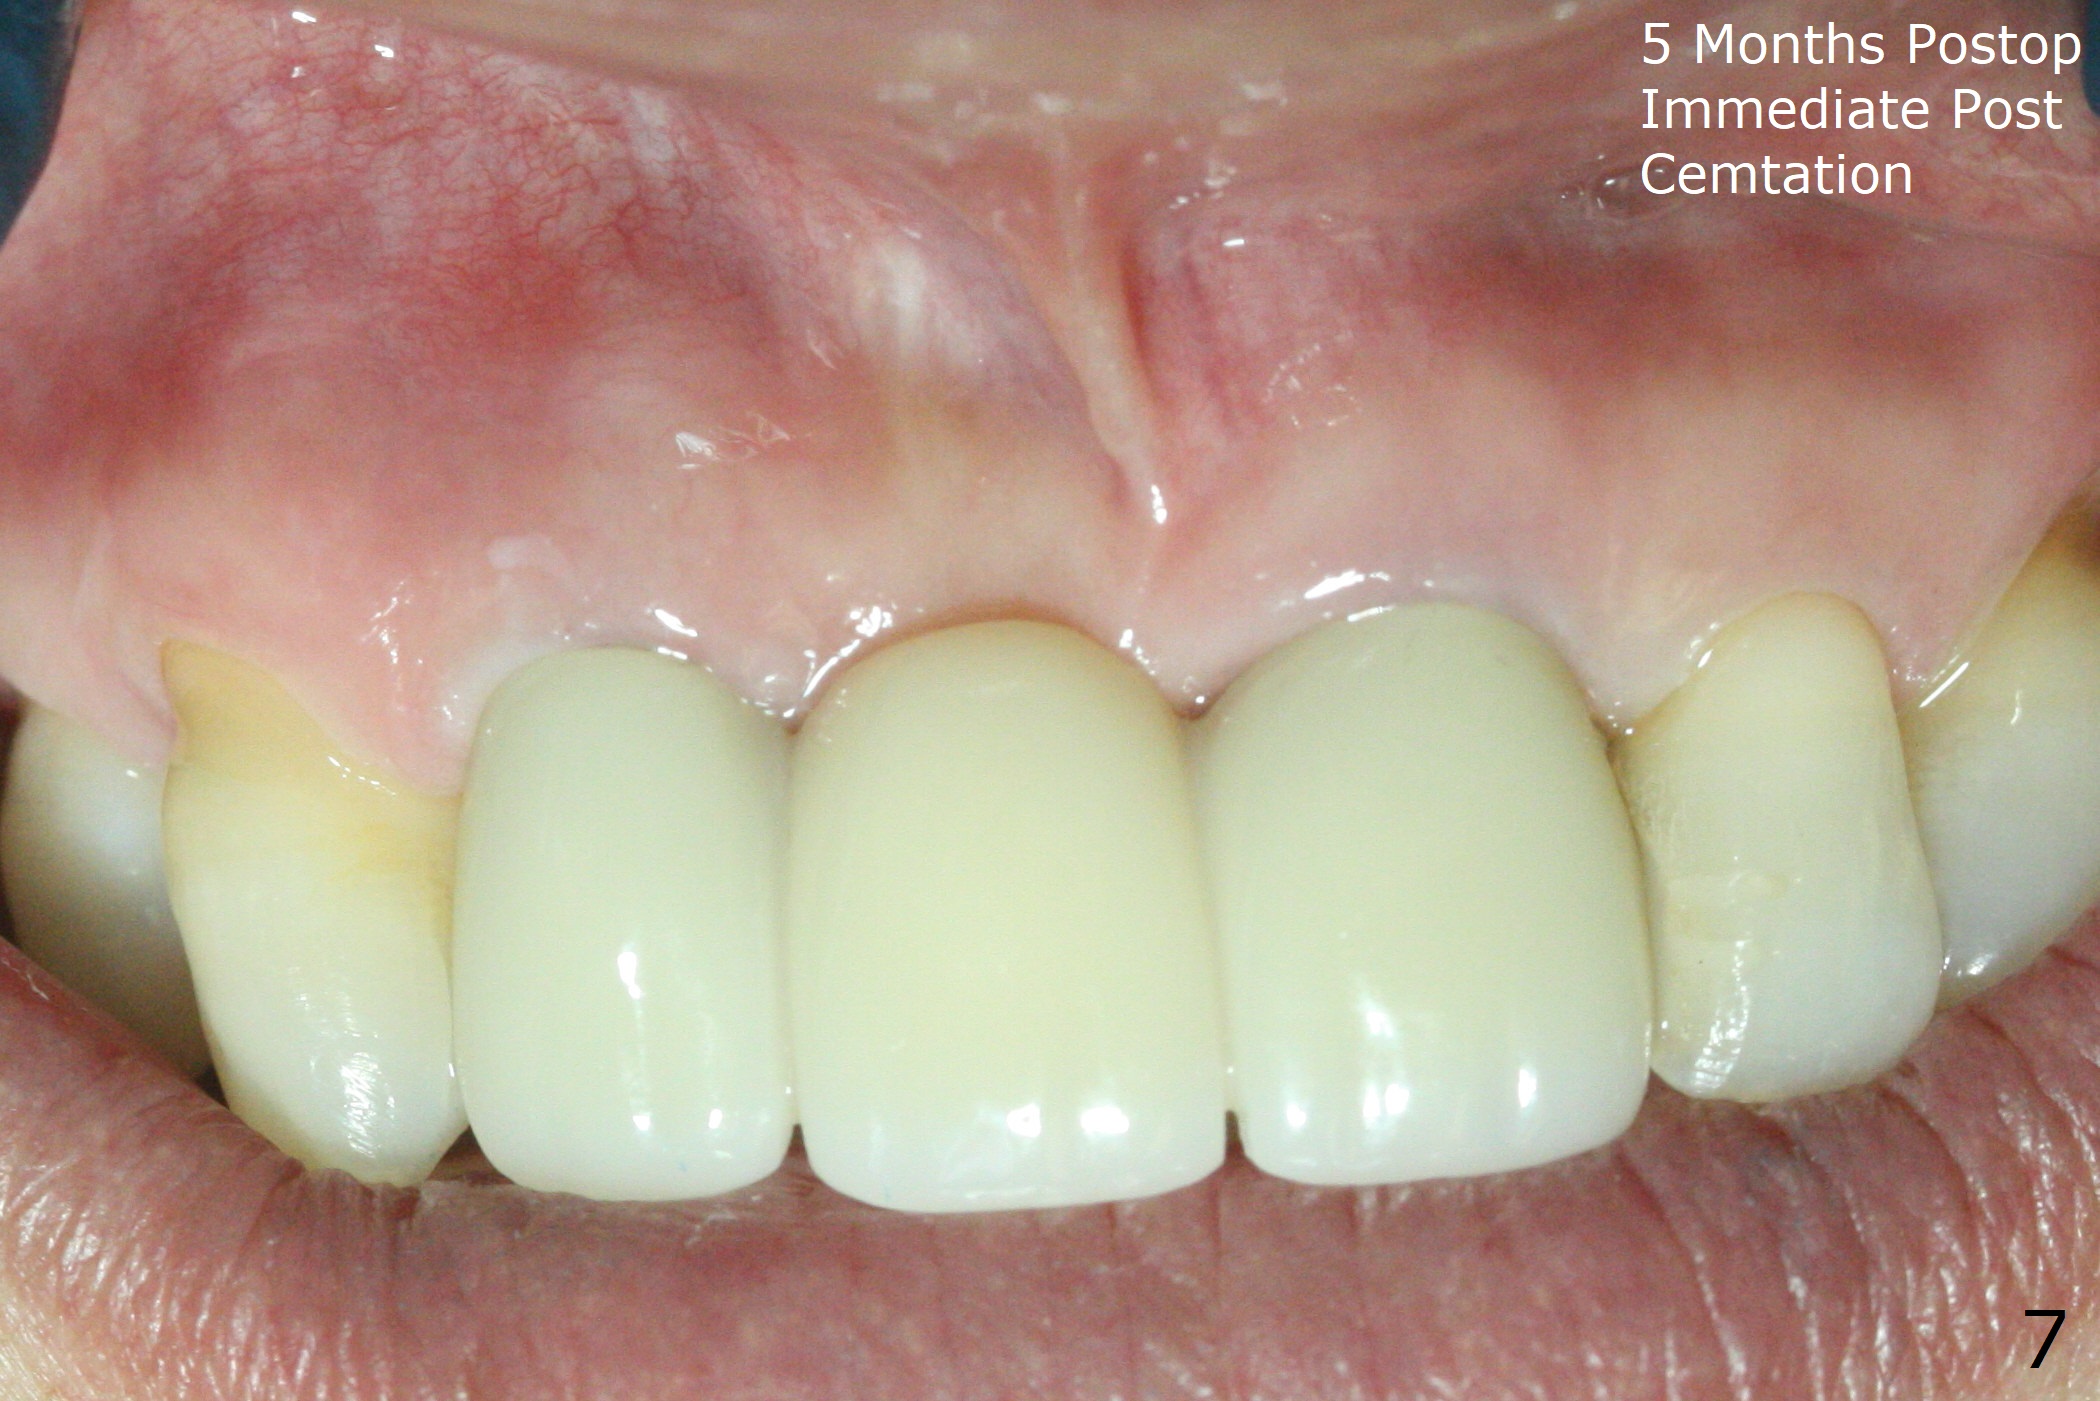

Since the pontic (Fig.1 #8) of the existing failed FPD has severe buccal concavity (*), socket shield is performed when #7 and 9 are extracted (Fig.2,3 *). Angled abutments are placed when 3.5x13 mm implants are inserted with guide. An immediate provisional FPD is fabricated. Acrylic is added to the pontic of the temporary FPD (Fig.4 arrow) to form a concave pontic gingiva (blanch)16 days postop. The patient returns 3.5 m postop with concern over temp being bulky and turning yellow. With Cetacaine and 1-0 cord, labial reducion is done for 7,9 abutments as well as 7 incisal reduction. The provisional is relined to increase 7 8 crown length. Next visit we will continue modification of temporary. Photos will be taken before and after modification (buccal and incisal views). The patient complains of occasional pain at #7. Check whether the socket shield at #7 is a culprit. In fact the implant at #7 is normal. Manipulation of the provisional does not help cosmetics much. A permanent restoration is delivered 5.5 months postop (Fig.7-9).